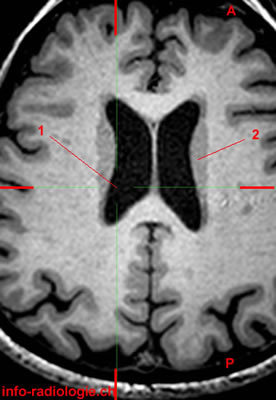

What are the black spaces at each side?

Lateral ventricles

What is the bulbous projection on the floor of the lateral ventricle?

Caudate nucleus

What is E?

Septum pellicidum

What is F?

Fornix